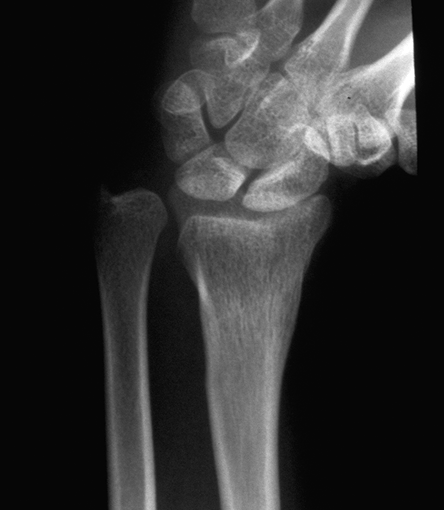

Case 2 Preop